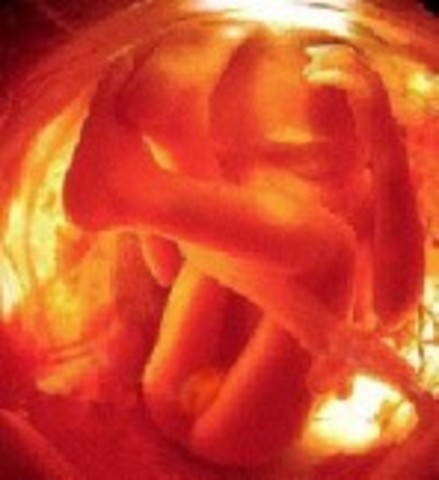

• Week 28

Week 28

Hair is visible through 4D ultrasounds. Milk teeth have started growing under the gums and eyes start to move.